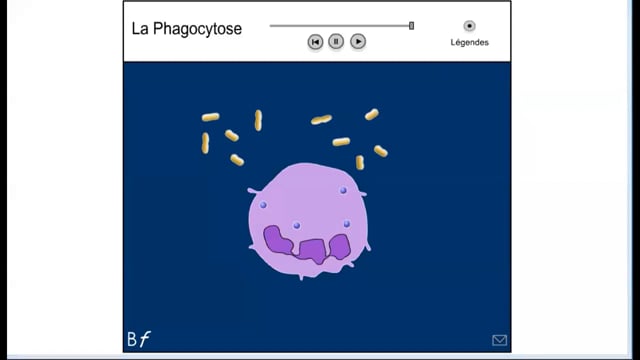

Sciences SVT